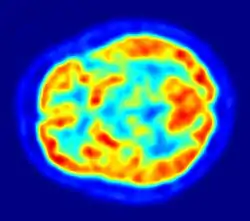

Brain Electrical Oscillation Signature Profiling (BEOSP or BEOS) is an EEG technique by which a suspect's participation in a crime is detected by eliciting electrophysiological impulses.[1][2]

It is a non-invasive, scientific technique with a degree of sensitivity and a neuro-psychological method of interrogation which is also referred to as 'brain fingerprinting'.

The human brain receives millions of arrays of signals in different modalities, all through the waking periods. These signals are classified and stored in terms of their relationship perceived as function of experience and available knowledge base of an individual, as well as new relationship produced through sequential processing. The process of encoding happens primarily when the individual directly participates in an activity or experiences it.[6]

It is found that when the brain of an individual is activated by a piece of information of an event in which he/she has taken part, the brain of the individual will respond differently from that of a person who has received the same information from secondary sources (non-experiential).[8]

BEOSP is based on this principle, thereby intending to demonstrate that the suspect who have primary encoded information of those who have participated in the suspected events[9] will show responses indicating firsthand (personally acquired) knowledge of the event.

University of Pennsylvania conducted a research along with the Brigham & Women's Hospital (Boston, Massachusetts), Children's Hospital Boston & the University Hospital of Freiburg, Germany which determined that Gamma Oscillations in the brain could help distinguish false memories from the real ones. Their analysis concluded that in the retrieval of truthful memories, as compared to false, human brain creates an extremely distinct pattern of gamma oscillations, indicating a recognition of context based information associated with a prior experience.[10]